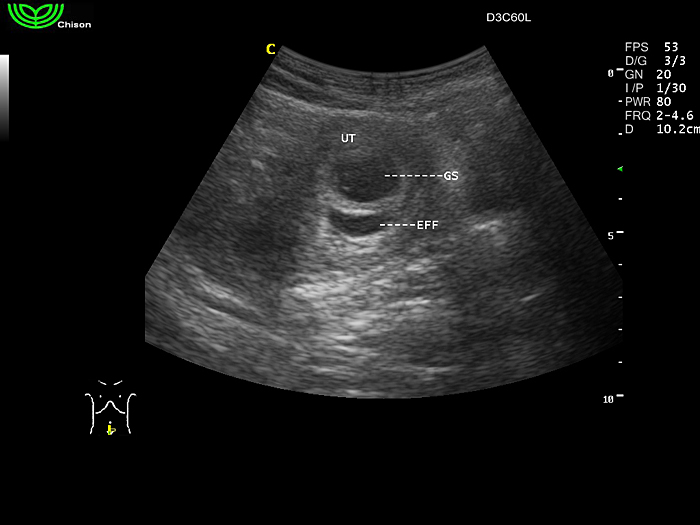

D3C60L 3.5МГц, конвексный.

2.0МГц - 5.8 МГц. Применения: абдомиальное обследование, акушерство, гинекология, обследование районной блокады нерва, осуществление и управление биопсией. |